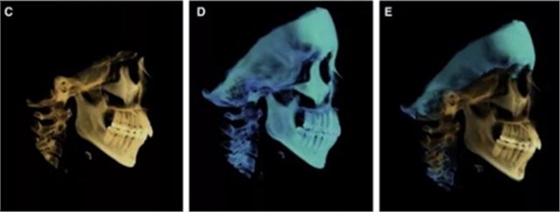

頭側(cè)分析提示為骨性安氏II類(ANB,8.4°;Wits,3.6mm),高角(SN-MP,44.9°),上頜切牙略舌傾(U1-SN,96.2°),下頜切牙略舌傾(IMPA,88。3°)(圖2;表)

治療后頭側(cè)數(shù)據(jù)提示:無明顯骨性變化(上頜SNA82.1°,下頜SNB74.9°),上頜前牙得到內(nèi)收,略舌傾,頦部前后位置無明顯改變,仍未凸面型(圖8,表)。將治療前后圖像重疊后結(jié)果如(圖8及圖9),24月后隨訪結(jié)果見圖10.